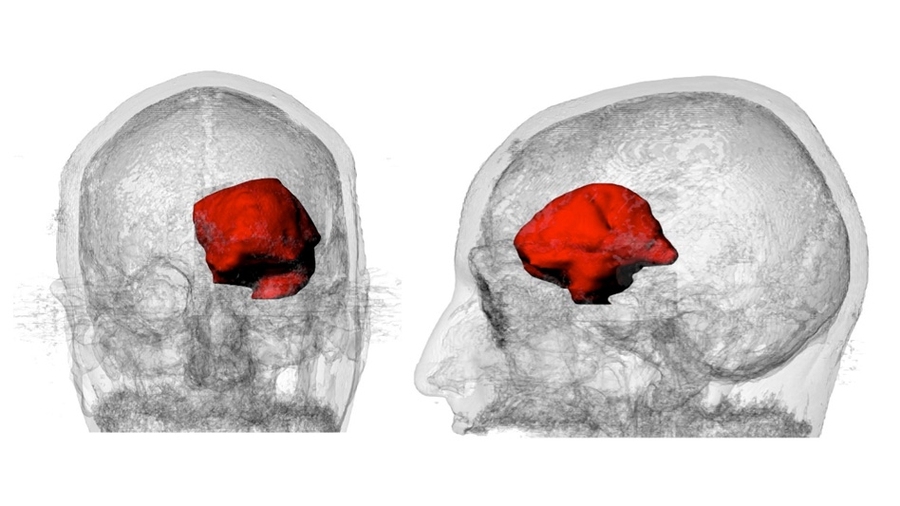

A 3-D visualization of Keating’s MRI data with the large astrocytoma tumor highlighted in red.

Caption: A 3-D visualization of Keating’s MRI data with the large astrocytoma tumor highlighted in red.

Credits: Image courtesy of James Weaver, Ahmed Hosny, and Steven Keating

Image courtesy of James Weaver, Ahmed Hosny, and Steven Keating